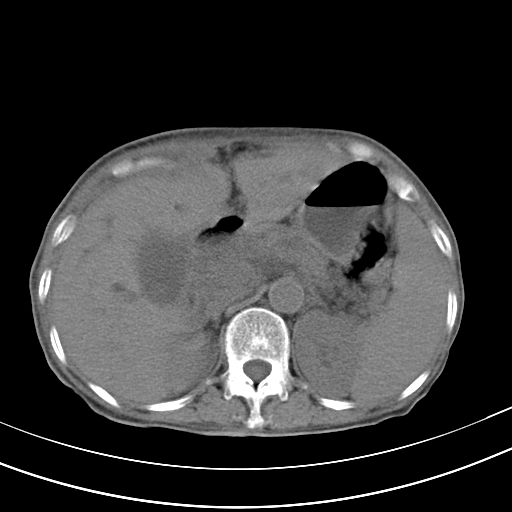

病人上腹部胀痛拌全身黄染八天

右侧少量胸水,胆囊增大,肝内胆管扩张,肝门部结构杂乱,建议增强。

肝内胆管及胰管扩张考虑为胰头区占位,肝门淋巴结增多,肝内多发低密度影,考虑为转移。门脉高压,脾大,胆囊大。

肝内胆管及胰管扩张,胰头增大考虑为胰头区占位,肝门淋巴结增多,考虑为转移。建议增强,脾大,胆囊大,壁厚,慢性胆囊炎。胃壁好像也增厚,且有一肿物。

1)考虑胰头癌并胆系低位梗阻;建议行ct增强扫描检查。2)慢性胆囊炎。3)脾大。4)少量腹水。5)双侧少量胸腔积液。